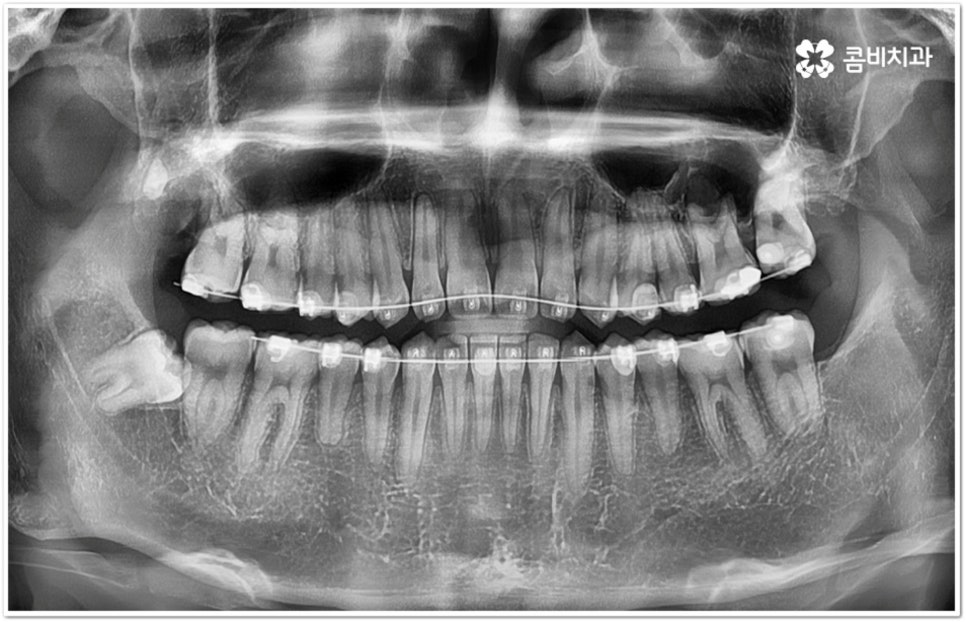

만약 똑바로 자라나고 관리가 용이하며 마주보는 대합치 역시 정상적으로 맹출되었다면 사랑니를 꼭 발치할 필요는 없을 거예요. 그러나 보통 사랑니는 사람의 치아 중에 가장 마지막에 나오는 치아라서 이미 구강 내 공간이 비좁은 상태이기 때문에 비스듬하게 자리를 잡고 일부분만 맹출이 되는 경우가 많이 있어요. 보통 머리가 앞쪽으로 기울어진 근심위로 자리잡는 케이스가 가장 많으며 그 밖에도 치아 머리가 뒤쪽으로 기울어져 있거나 혀쪽, 볼쪽으로 누운 케이스, 아예 옆으로 완전히 누운 케이스 등도 발견되고 있는데요.

잇몸에 반쯤 덮힌 채로 삐뚤게 나온 사랑니는 칫솔질을 제대로 하기 어렵고 위생 관리가 잘 되지 않아 주변 잇몸에 염증이 생기기 쉬우며 어금니까지 충치가 번질 위험이 높아지게 되어 구강 건강 관리 및 예방 차원에서 발치 처치를 해주실 필요가 있어요. 발치 난이도는 사랑니의 경사 각도와 방향 및 치아 뿌리의 길이와 개수, 사랑니 뒤쪽 턱 뼈의 각도 및 형태, 하치조 신경 또는 상악동까지의 거리 등에 따라서 달라질 수 있습니다.

이때 아래사랑니발치 의 경우 아래턱 부근을 지나가는 큰 신경인 하치조 신경을 건드리지 않고 조심스럽게 사랑니만 제거해야 하기 때문에 3D-CT 등 정밀 검진 기계를 통해 사랑니의 매복 위치, 깊이, 각도 등의 상태와 신경까지의 거리 등을 먼저 꼼꼼하게 파악한 후에 발치를 해 줄 필요가 있는데요. 만약 완전히 매복되어 있다면 사랑니 주변에 함치성 낭종이 발생할 수도 있는데 이로 인해 주변 치조골이 파괴되고 어금니 쪽으로 병변이 확산되면 결국 치아를 상실하게 되거나 턱뼈가 약해져서 작은 충격에도 부러지는 현상이 발생할 가능성도 있으므로 될 수 있는대로 치료 시기를 놓치지 않는 것이 중요한 포인트라고 할 수 있어요.

아래사랑니발치 와 다르게 윗 사랑니 발치 시에는 상악동까지의 거리가 너무 짧을 경우 천공 및 감염의 위험이 있으니 이에 대해서 3D CT 를 통해 꼼꼼하게 확인하고 환자분들의 상황에 맞는 치료를 진행할 필요가 있어요. 예를 들어 사랑니로 인한 문제가 크지 않은 경우 그대로 두고 지켜볼 수도 있고 다른 치료를 하는 중에, 즉 교정이나 임플란트 등을 진행하는 과정에서 발치가 꼭 필요한 경우라면 상악동 거상술, 뼈이식 등의 치료를 선행하여 무리하지 않게 뽑아주는 것이 좋을 거예요.

교정 치료를 하기 전에 사랑니를 먼저 발치해야 하는지 문의주시는 분들이 있는데 이 역시 검진 후에 환자분들의 상황에 맞게 결정하는 것이 좋기 때문에 교정과 사랑니 발치에 두루 임상 경험이 풍부하신 의료진을 선택하시면 치과를 옮겨다니는 번거로움 없이 보다 편안하게 적기에 필요한 치료를 받으실 수 있습니다. 또한 처음부터 끝까지 책임지고 철저하게 케어해 주는 치과의 도움을 받으시면 업무 때문에 많이 바쁘신 직장인 분들의 경우 시간을 단축시킬 수 있어 좋을 뿐 아니라 환자분들이 느끼실 수 있는 여러가지 심적인 부담도 덜 수 있을 거예요.

관리하기 까다롭기 때문에 위 아래사랑니발치 를 해 주는 것이 보통이긴 하지만 간혹 사고로 어금니를 상실하거나 유전적으로 어금니가 없으신 분들의 경우 교정 치료를 통해 어금니 대신 사용하는 사례가 있으니 필요하다면 발치 결정 전에 꼼꼼하게 검진을 받아보실 필요가 있어요.

모든 경우에 사랑니가 어금니를 대신할 수는 없으며 사랑니로 어금니를 대체하기 위해서는 사랑니의 상태, 이동 가능 공간, 주변 구조물 및 전체 구강 구조 등 환자분들의 상황을 먼저 면밀하게 살펴본 후 교정 치료 계획을 세심하게 세워 잇몸과 사랑니의 손상 없이 치료할 필요가 있으므로 고난도 과정에 맞게 술자의 높은 숙련도가 요구되는 만큼 노하우가 풍부한 의료진을 선택하시길 권유드리고 있습니다.